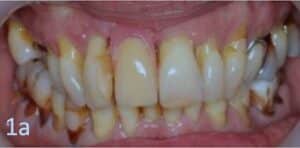

Une patiente de 55 ans, en bonne santé et non fumeuse, présentait une mobilité dentaire généralisée et une récession gingivale. Des examens cliniques et radiologiques (Fig. 1a, 1b) ont été réalisés. Un diagnostic de parodontite généralisée de stade 3, grade B 2, a été posé. La maladie parodontale a été traitée et l’état maxillaire a été stabilisé par un traitement endodontique et la pose de bridges provisoires.